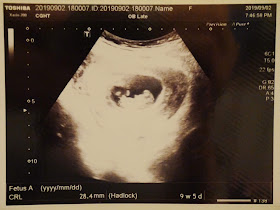

2019/9/2(9W)台北長庚初診

因為是高齡又是雙胞胎,所以我們就由王醫師推薦的幾家大醫院選擇了專精高危險妊娠的婦產科醫生,在9週的時候就到台北長庚找蕭醫師看診。

初次產檢做了一些常規的檢查,CRL一個是2.84cm;一個是2.85cm。